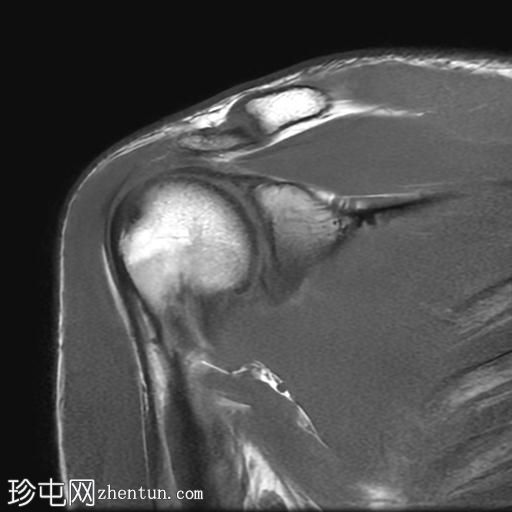

右肩外伤。

年龄:25岁

性别:男

MRI

冠状位

T1加权像

Bankart损伤伴前盂唇及下方骨髓水肿

Hill-Sachs缺损表现为骨性压陷,肱骨头后外侧及下方骨髓水肿/挫伤

冈上肌腱关键区纤维肌腱病

MRI结果符合肩关节前脱位伴Hill-Sachs缺损和Bankart损伤的

影像

学表现。